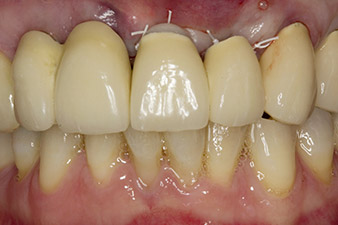

Lorsque le patient s'est présenté pour la première fois, les dents 21, 22 et 23 avaient été restaurées il y a 19 ans à présent, par des couronnes jumelées collées sur les implants en position 12/11 à l'aide d'une attache

(cf. Fig. 2).

La dent 23 présentait une fracture coronaire horizontale et un matériau de reconstitution du moignon et de scellement des tenons a été utilisé à titre de restauration temporaire. L'objectif était de poser un bridge en oxyde de zirconium sur les implants existants aux positions 12 et 11 et de poser deux nouveaux implants aux positions 22 et 23.